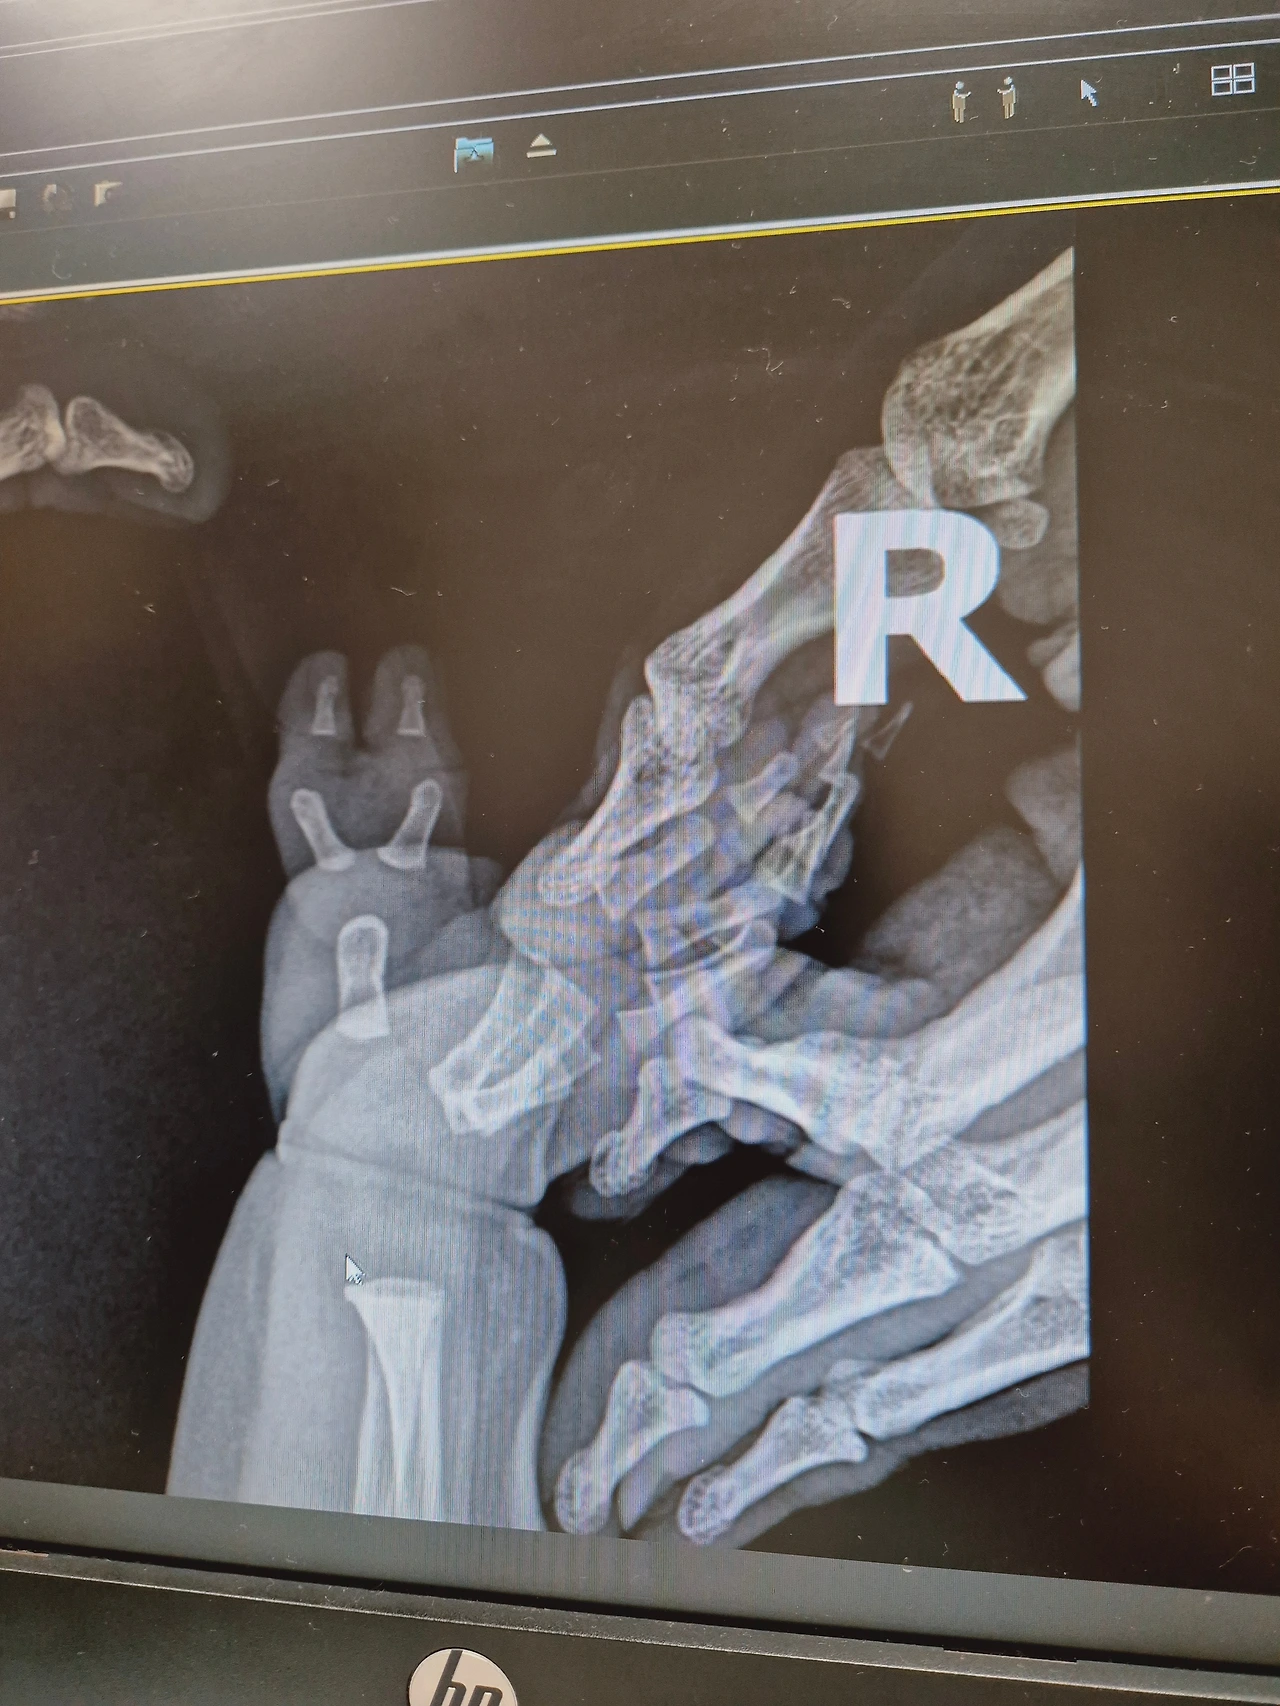

오른쪽 손은 x-ray 선생님의 손이다. 아기를 위해 본인도 방사능을 맞고 계시는 대단하신 분이다.

둘째가 3개월이 되었을 무렵 우리는 다지증 수술 명의가 계신 병원의 초진을 다녀왔다. 겉으로 볼때 '아.. 6번째 손가락에 뼈가 있구나'를 이미 알고 있어서 X-ray 결과지를 볼 때는 역시 맞구나 싶었다. 문제는 엄지의 기능을 하게 될 손가락의 뼈가 약간 휘어있어서 혹시나 2차 수술을 하게 될지도 모른다는 거였다. 한 번의 수술로 손가락이 올곧게 제 기능을 하길 바랄 뿐이다.

어쨌든 둘째의 6번째 손가락은 다른 다지증 아기들에 비해 좀 난이도가 어려운 편에 속한다. 수술은 아기가 어느 정도 크고 해야했기에 수술 일정만 잡고 나왔다.